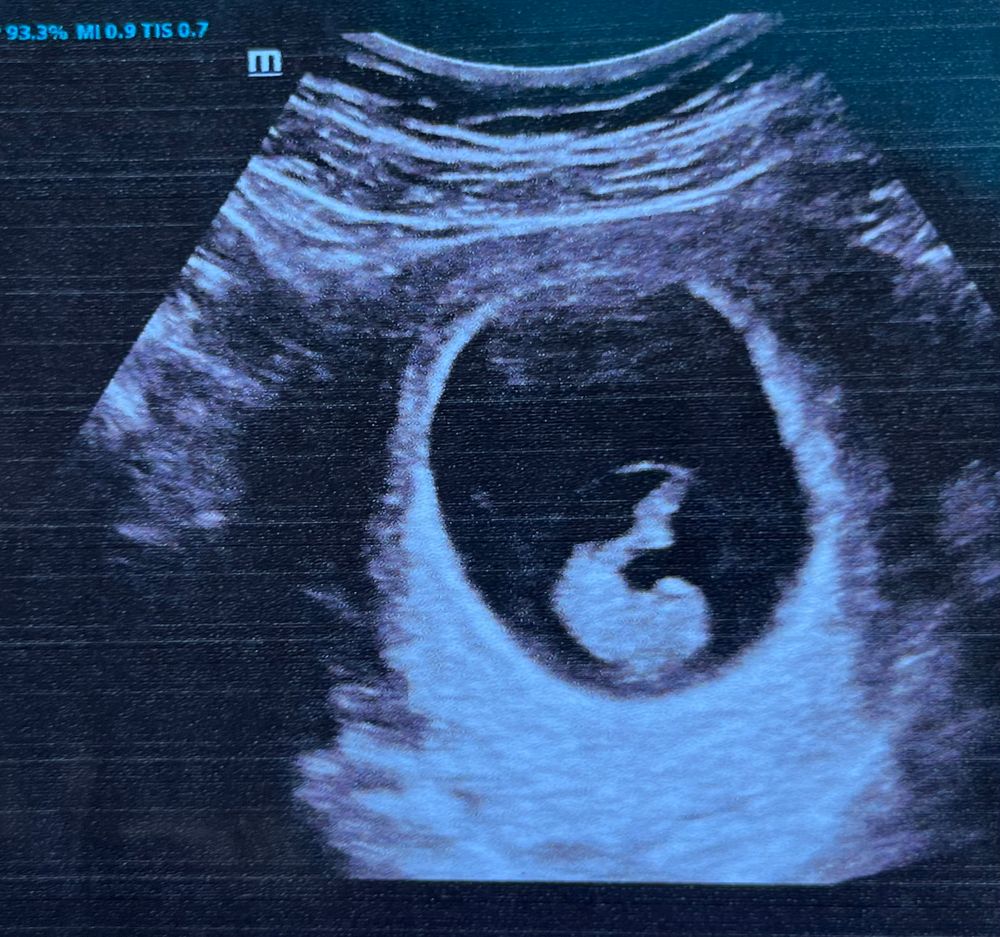

Результаты: УЗИ, КТГ, доплера, скринингаВсем привет ❤️ сегодня была на узи. С малышом все хорошо. Уже 2,3 см. Сердечко (чсс) 173 удара. У нас почти сформировалась пуповина.

Увидела шевелюшки. Акушерский срок 8 недель 6 дней, эмбриональный 9 недель 😁